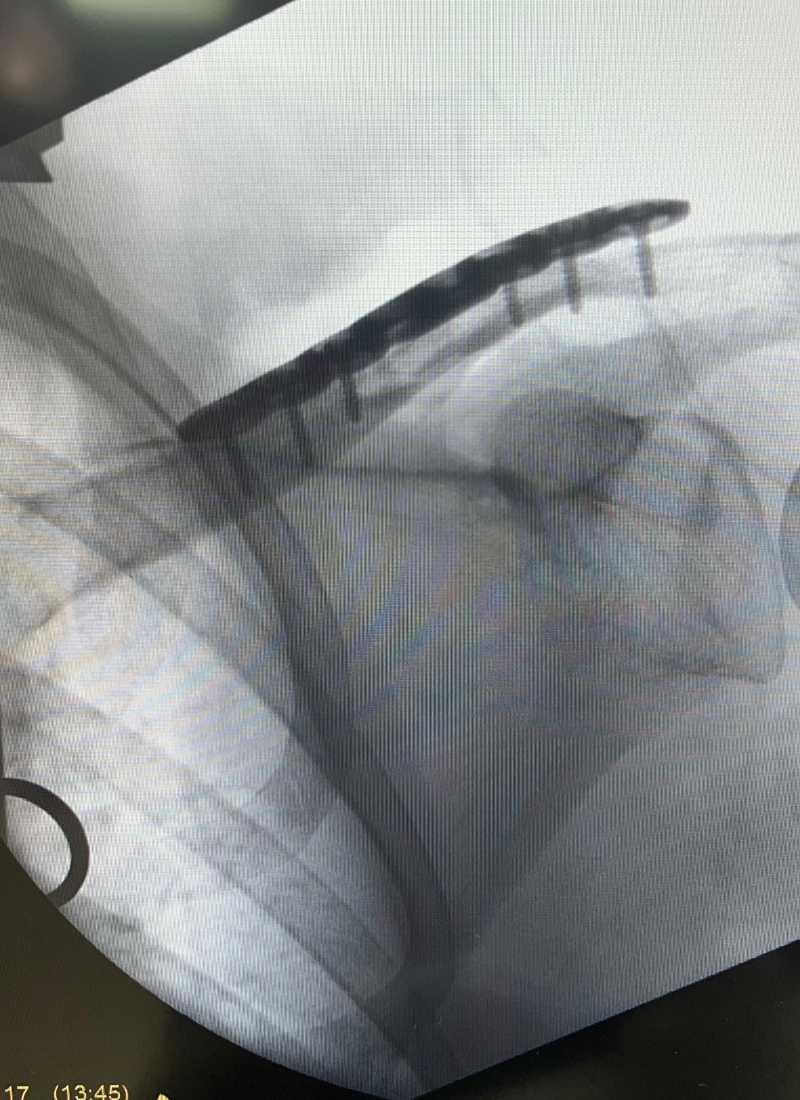

Minimally Invasive Fracture Surgery

Whenever appropriate, Dr. Arroyo employs minimally invasive surgical techniques. These approaches involve smaller incisions, which can lead to less pain, reduced blood loss, lower risk of infection, and a faster recovery compared to traditional open surgery.

Internal and External Fixation Techniques

Internal Fixation:

This involves using specialized implants like plates, screws, rods (intramedullary nails), or wires to stabilize the broken bone fragments from within. These devices hold the bone in proper alignment while it heals.